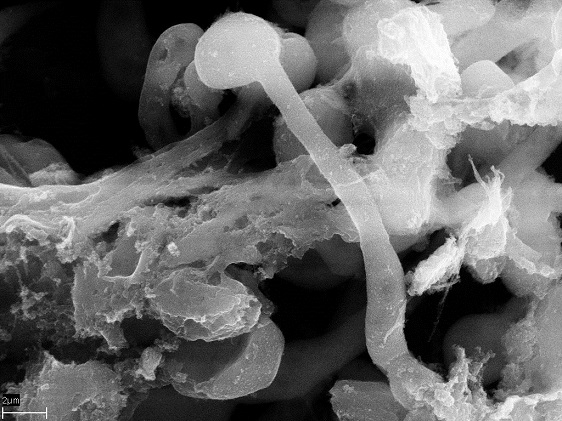

Den vanliga svamparten Candida albicans utgör ett växande hälsoproblem för personer med nedsatt immunförsvar. Svamparten har förmågan att växa som antingen en rund eller trådlik form. Den senare formen är mer smittsam och invasiv. En viktig del av kroppens immunförsvar är neutrofiler, en vanlig sorts vita blodkroppar som utvecklat flera olika strategier för att bekämpa de två olika formerna av svamparten. Neutrofiler spårar upp och slukar svampcellerna eller utsöndrar en antimikrobiell substans som dödar dem. Dessutom kan neutrofiler svara genom att släppa ut nätliknande fällor som gjorda av DNA-strängar och fyllda med antimikrobiella proteiner. Så kallade neutrofila extracellulära fällor (NET) kan fånga och döda svampceller. Men neutrofiler kan också svara genom att okontrollerat släppa ut fällor, vilket skadar kroppsvävnad och är associerat med inflammatoriska sjukdomar såsom systemisk lupus erythematosus (SLE) och åderförkalkning.

Bild: Candid albicans hyphae-celler i en neutrofil extracellulär fälla. (foto: Constatin Urban)